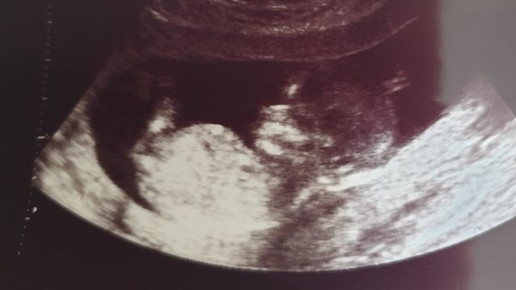

Ist die Schwangere dann zwischen der neunten und zwölften SSW angekommen erfolgt die zweite Untersuchung mit der bereits genannten Routine. Hier kommt oft der künftige Vater mit, denn der Frauenarzt führt zu diesem Zeitpunkt den ersten Bauchdecken-Ultraschall durch. Jetzt kann man schon gut erkennen, ob es sich um einen sogenannten Einling oder eine Mehrlingsschwangerschaft handelt. Ab der neunten SSW spricht man nicht mehr von einem Embryo, denn mit der Ausbildung der inneren Organe wird der Nachkomme zum Fötus. Die Kindslage wird wie auch die Herzaktion und die Länge des Kindes in den Mutterpass eingetragen. Wichtig ist die zeitgerechte Entwicklung zu überprüfen. Zwischen der elften und der dreizehnten SSW kann der Frauenarzt ein sogenanntes Ersttrimester-Screening anbieten.

Beim vierten Termin steht wieder ein Ultraschall an. Hier kann der sogenannte Feinultraschall durchgeführt werden, bei dem sich nicht nur Wachstum und Entwicklung des Kindes sondern auch Auffälligkeiten an den Organen feststellen lassen können. Er kann beim behandelnden Frauenarzt durchgeführt werden, wenn dieser die entsprechende Zusatzfortbildung absolviert und die passenden Geräte in seiner Praxis hat. Ansonsten fährt die Schwangere dafür in eine Klinik. Auch die Plazenta und die Fruchtwassermenge wird bei diesem Ultraschall beurteilt. Die Ergebnisse trägt der Arzt in eine Normkurve im Mutterpass ein. Bei dieser Untersuchung kann man schon häufig das Geschlecht des ungeborenen Kindes erkennen.